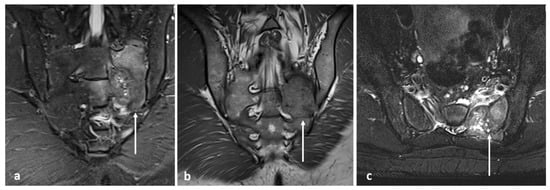

| Giant cell tumour | Mixed cystic and solid expansile lesions, with thin peripheral bony shell. ‘Soap bubble’ appearance. | Secondary ABC change is common, with fluid—fluid levels. Intermediate to low signal intensity on both T1 and T2. Enhancing soft tissue component. |